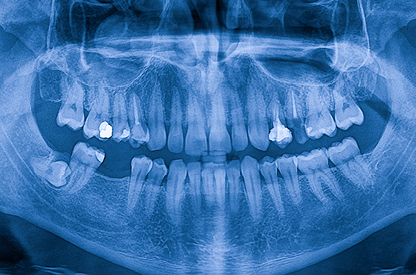

This one-day Dental Cone Beam Computed Tomography (CBCT) 2B course offers an interactive, participant-centred approach to learning and will enable you to maintain the safe operation and interpretation of CBCTs.

The Dental Cone Beam CT 2B course will include a focused session on bone disease and their presentation on dental imaging, radiological interpretation exercises and extensive peer learning, discussion and reflection on CBCT reporting skills.